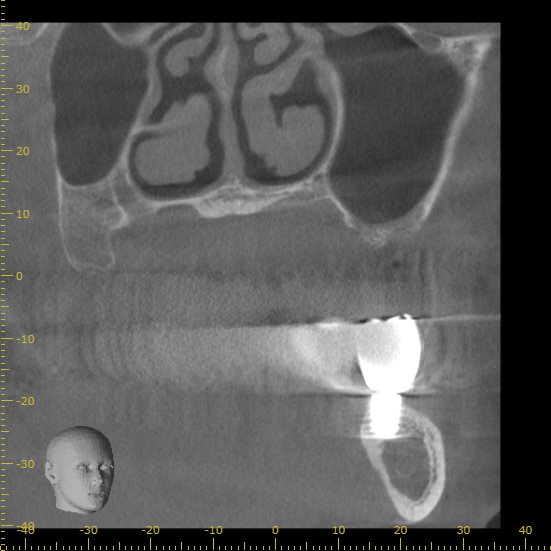

正面から見たCT画像です。

今回の画像をみるとわかりますが、骨が極端に少ない状態です。

正面から見た画像です。

インプラントの半分以上に骨が足りない状態です。

現状の骨の状態でインプラントを行うこと自体が難しいと判断できます。

この場合は骨を造成し、インプラントを埋入するための土台を作る必要があります。

今回サイナスリフトと呼ばれる術式をインプラントの手術と併用して行う計画を立てました。